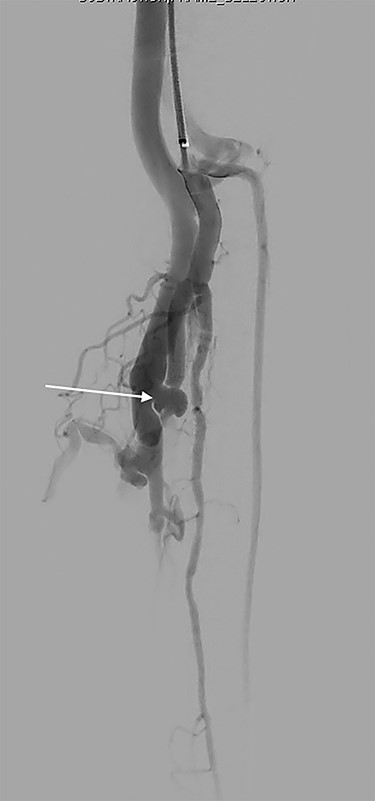

Formal angiogram was undertaken and posterior tibial AVF was confirmed (Fig. 1). Two Advanta V12 polytetrafluoroethylene covered balloon-expandable stents were placed in the posterior tibial artery (Merrimack, NH, USA): 5 × 22 mm distally and 6 × 22 mm proximally, resulting in successful exclusion of the fistula (Fig. 2).

A covered stent (arrow) deployed in the posterior tibial artery occludes flow through the fistula. Contrast flows into the arterial tree without shunting into the venous system.